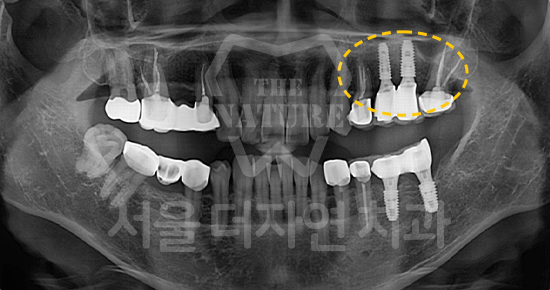

#Sinus Lift

• BEFORE: 2021.02.01

• AFTER: 2021.05.13